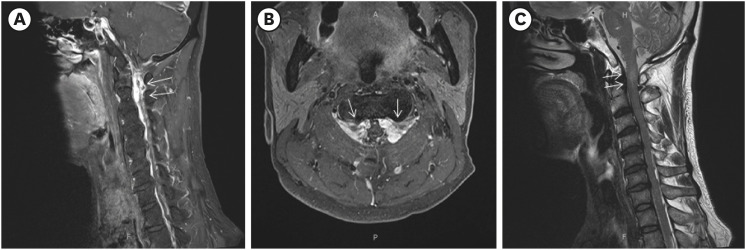

We present a case of cervical myelopathy caused by epidural hematoma formation due to chronic cerebrospinal fluid overdrainage. A 55-year-old man who underwent ventriculoperitoneal (V-P) shunt surgery for normal pressure hydrocephalus presented with progressive weakness of both the upper and lower extremities. Magnetic resonance imaging (MRI) revealed compressive myelopathy at the cervicomedullary junction at the C1-C2 level caused by epidural hematoma formation due to intracranial hypotension (IH) caused by a complication of V-P shunt. He underwent decompressive laminectomy and hematoma removal at C1-C2 and replacement of the V-P shunt valve. Follow-up cervical spine MRI showed an improved state of severe central spinal stenosis at the C1-C2 level and an improved state of compression-related cord signal intensity change in the spinal cord. After surgical intervention and intensive rehabilitation, the patient showed clinical improvement. If cervical myelopathy is suspected in patients with a shunt, cord compression due to venous engorgement or hematoma caused by over-shunting and IH should be considered.

Abstract Image